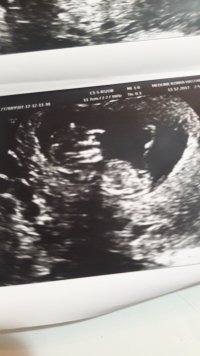

12+6 haftalık . Cinsiyetini yorumlayabilirmisinjz.dr um tam göremediği için birşey diyemedi. IMG-20171227-WA0007.jpeg IMG-20171227-WA0003.jpeg

Merhaba esila , yüklemiş olduğunuz görselde nub çıkıntısı belirgin değil. Dolaysıyla değerlendirme yapamıyoruz . Bebeğin cinsiyeti 16-17- 20 . haftalarda net olarak izlenebilir. Sağlıklı gebelik geçirmeniz dileği ile.